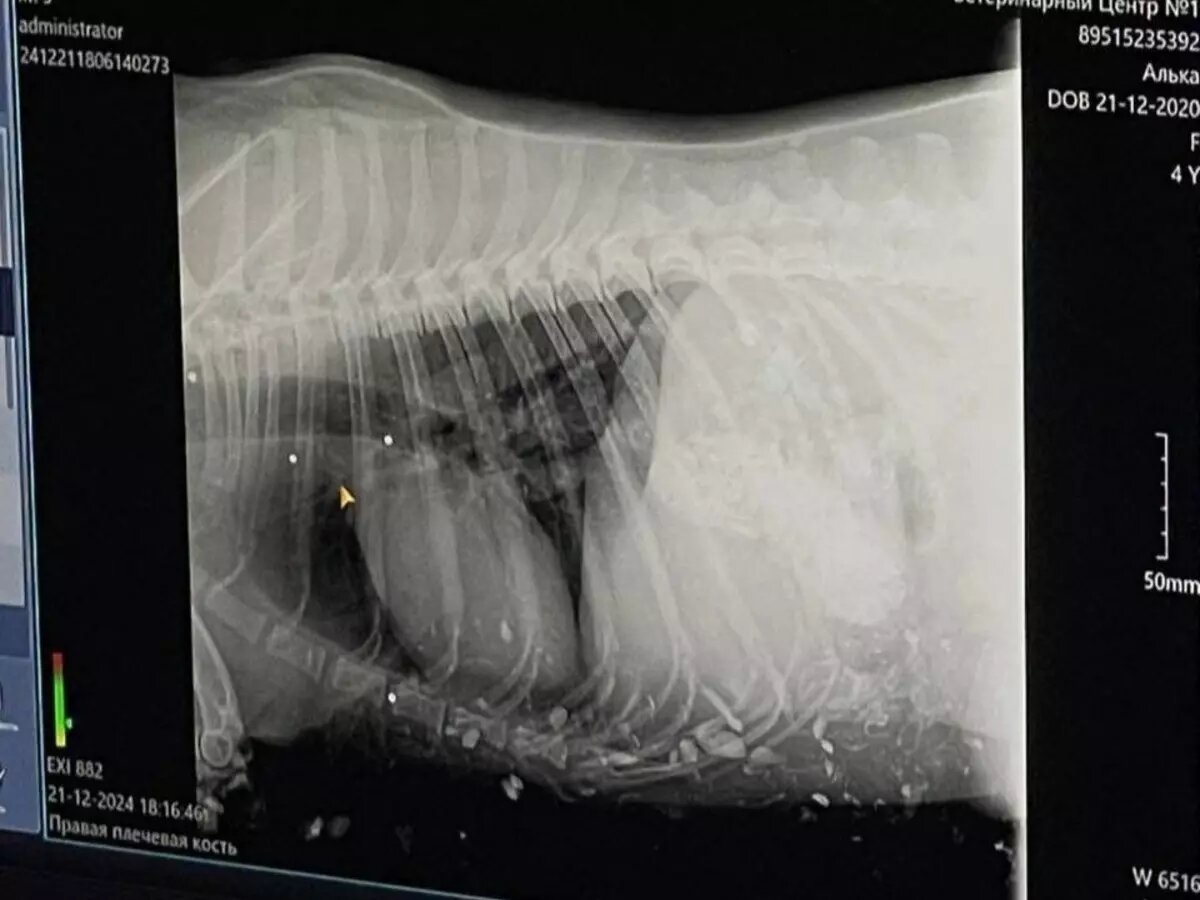

По словам хозяйки, обессиленный пес лежал на земле. А по всему телу были красные пятна крови. В ветеринарной клинике Анастасии сказали, что в ее собаку кто-то выстрелил 15 раз.

Ветеринар вытащил маленькие пули из трахеи, головы, правой лапы и зоны около глаз. Сейчас животное еще проходит реабилитацию.